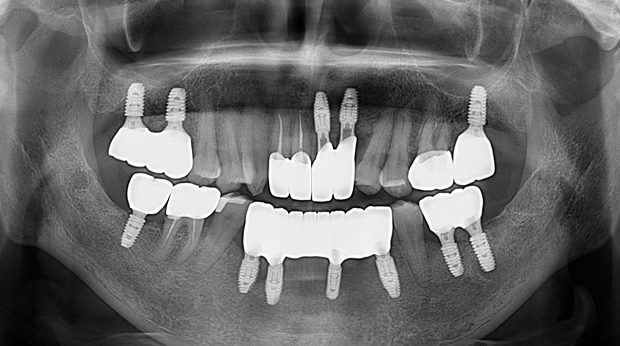

의식하진정법(수면마취)/임플란트

수술 담당 구강악안면외과 전문의

고난도 수술 진료

임플란트와 사랑니 발치는 외과적 시술로 잇몸을 절개하는 외과적 시술은

짧으면 짧을 수록 시술 후 붓기와 통증이 최소화됩니다.

치과의사 경력 14년차 구강외과 전문의가 빠르고 안전하게, 아프지 않게 수술해 드립니다.

치과경력 14년차 구강외과 전문의

연세대학교 치과대학 구강외과 임상 조교수